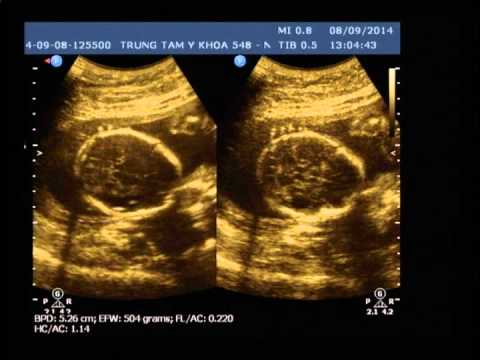

HÌNH ẢNH ĐẦU TIÊN CỦA HAI CON YÊU

Đi siêu âm bác sỹ bảo hai con là con trai, Ba rất vui nhưng vẫn hồi hộp chờ ngày con chào đời.